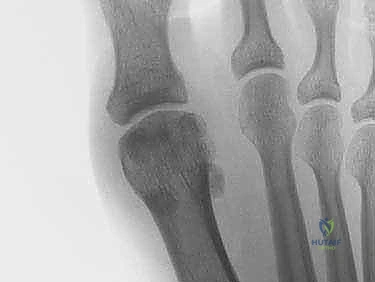

2. التصوير بالأشعة السينية (X-Rays)

يتم إجراء صور أشعة سينية بوضعيات تحمل الوزن (Weight-bearing) وبوضعيات الإجهاد (Stress views). تساعد الأشعة السينية في:

* استبعاد وجود كسور في عظام المشط أو السلاميات.

* تقييم العظام السمسمانية (البحث عن كسور أو هجرة غير طبيعية للعظام السمسمانية، مما يدل على تمزق الصفيحة).

* تقييم تضيق المسافة المفصلية.